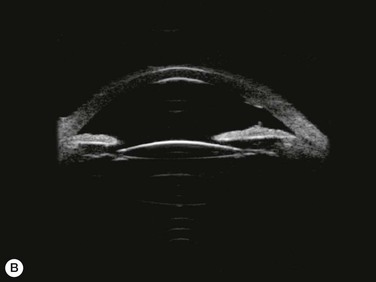

Substantial increases in anterior chamber depth and angle width following cataract extraction with intraocular lens (IOL) implantation have been demonstrated in eyes with PAC (Fig. 108-2A,B).23–25 The narrower the preoperative anterior chamber angle, the greater the alteration of angle configuration. Whereas iridolenticular contact was observed in a phakic eye, there was no iris and IOL contact in a pseudophakic one (Fig. 108-2A,B). The iris plane shifted backward, deepening the central anterior chamber by approximately 850 µm. Preoperative biometry performed in a series of 52 eyes of 48 consecutive Thai middle-aged patients who had developed acute PAC within 6 months showed that average natural lens thickness and central anterior chamber depth were 4.83 mm and 1.8 mm, respectively.26 Since the IOL (PMMA, silicone, acrylic) thickness in the 20–25 D power ranges from 0.75 mm to 1.42 mm. Replacement of the natural lens with the IOL provided up to 4 mm more axial distance within the anterior segment eliminating angle crowding and appositional closure. In addition, anterior chamber deepening with a viscoelastic during IOL implantation might break recent PAS.

Several studies have shown that extracapsular cataract extraction (ECCE) with IOL implantation is effective in opening the angle and controlling IOP in refractory PAC.27–30 Currently, ECCE has been replaced by phacoemulsification which offers a higher surgical success rate, less postoperative inflammation and fewer complications. In addition, the clear corneal approach spares the superior conjunctiva for possible filtering surgery, if needed. Phacoemulsification and IOL implantation has been reported to be highly effective in patients with uncontrolled PAC.31,32 However, up to 32% of the patients still had persistent PAS and required long-term treatment with glaucoma medication following lens removal either by ECCE or phacoemulsification and IOL implantation alone (Fig. 108-2A).5,32 Goniosynechialysis is the next step to eliminate the remaining synechiae and control the IOP (Fig. 108-2C).

Patients are treated with antiglaucoma medications and frequent topical steroids. When the inflammation subsides, the medications are then slowly tapered off within a month. Occasionally, a release of aqueous through the paracenteses at the slit lamp may be performed if a high IOP rise occurs. Gonioscopy typically reveals opening of the angle structures with irregular pigmentation on the newly exposed trabecular meshwork and the angle wall (Fig. 108-6). Angle recession or a cyclodialysis cleft are undesirable findings. If successful, anterior segment optical coherence tomography or ultrasound biomicroscopy should demonstrate separation of the PAS and reopening more than half of the entire angle (Figs 108-2, 108-7).